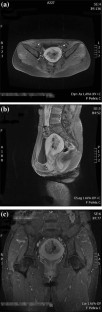

Fig. 1

Fig. 2

Fig. 3

Fig. 4

Fig. 5

Fig. 6